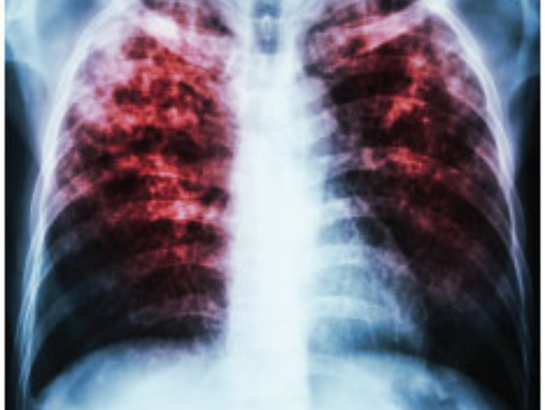

For diagnosis, Dr. Himabindu at Helios Lung Care offers various tests such as skin tests and blood tests, alongside imaging studies like chest X-rays or CT scans. Treatment for latent TB involves medications to prevent activation. However, drug-resistant TB requires longer, more intensive treatment, up to 30 months.